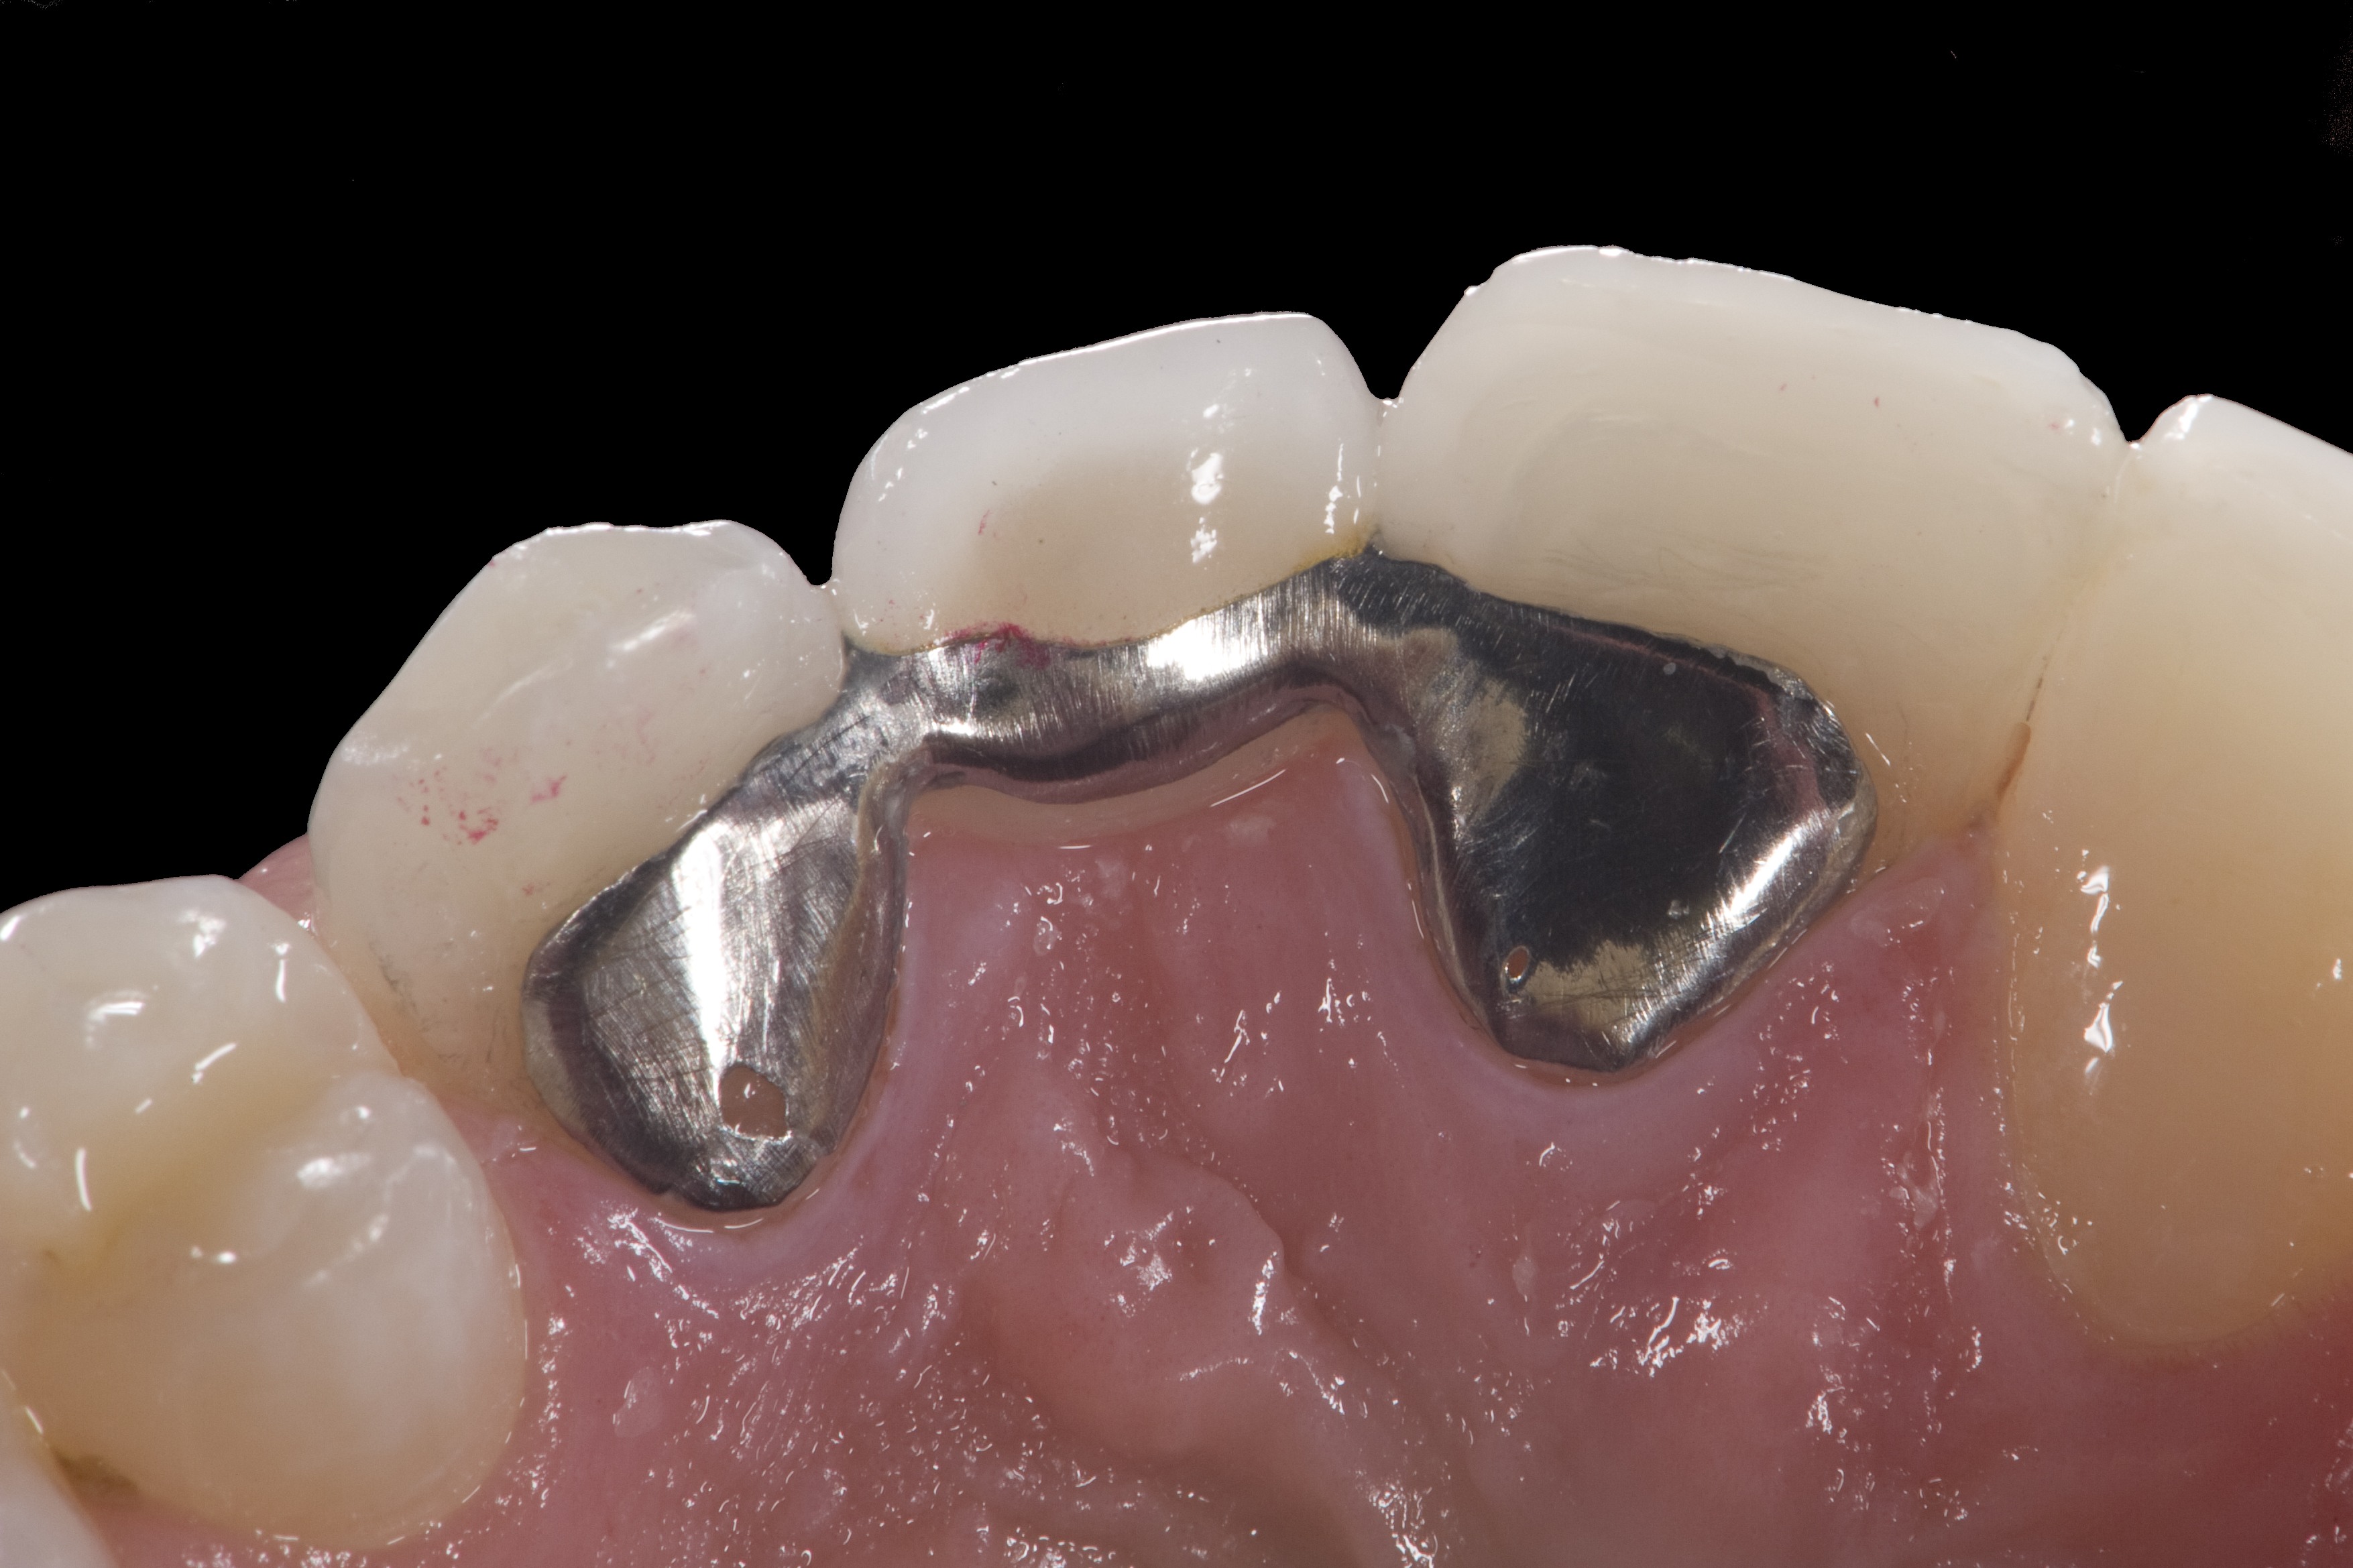

A 14-year-old patient presented to the office with his mother (Figure 1). His chief complaint involved the large spaces between the teeth created by his missing right maxillary lateral incisor and his small left maxillary lateral incisor. He desired to replace the missing tooth with an implant and create a beautiful smile. Upon examination, he was found to have a class I canine and molar relationship, but because he had a tooth size/arch size discrepancy and space distal to the right central incisor, the remaining incisors had drifted to the right. The left maxillary lateral incisor was peg-shaped and in a cross bite position. Studies have shown a clear association between congenitally missing teeth and reduced tooth size.59-62 Because he was only 14-years-old at the time and could not have implants placed until the cessation of growth (somewhere in the vicinity of 22 years old), he was sent to the orthodontist for alignment of the teeth.16,17 After 2 years of orthodontics, the appliances were removed, and his tooth coloration was improved using carbamide peroxide bleaching (Figure 2). Because some form of provisional needed to be placed until he was finished growing, a double-wing metal resin-bonded bridge was chosen. As discussed earlier, this is the ideal transitional prosthesis for patients that have congenitally missing maxillary lateral incisors. The benefits of this type of prosthesis include its ability to be removed and rebonded during the surgical phase of treatment and its ability to retain the roots in their proper position after orthodontic treatment.16 The final plan for the patient was to increase the width of the central and the maxillary left lateral incisor, utilizing porcelain laminate veneers to achieve the appropriate width/length ratio of 80%. A wax-up was created to idealize tooth size, a putty matrix was made from the wax-up to facilitate bonding of the incisors, and a non-precious, double-wing metal resin-bonded bridge was fabricated for lateral incisor replacement. Once the teeth were bonded to ideal size, the “Maryland Bridge” was fabricated from a polyvinyl arch impression with the newly bonded teeth (Figure 3). The metal frame was cast from a non-precious alloy to allow for fabrication of a very thin frame and to create a better surface for bonding. After sandblasting the internal aspect of the frame with CoJet™ silica (3M ESPE), accomplishing salinization, and executing cementation with a dual-cure resin cement, a fairly good adhesion to the frame was anticipated.29 The enamel surface was etched with phosphoric acid for 30 seconds, the primer (Single Bond Plus, 3M ESPE) was applied to both the internal surface of the sandblasted framework and the etched enamel, and the bridge was cemented with RelyX™ ARC (3M Espe) dual-cured resin cement (Figure 4 and Figure 5).

(4.) Double-wing metal resin-bonded (Maryland) bridge replacing the right lateral incisor (facial view).

Figure 4

(5.) Double-wing metal resin-bonded bridge replacing lateral incisor (lingual view).

Figure 5